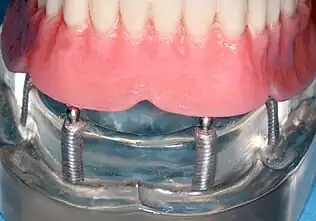

Four mandibular implants

Four lower implants to retain a complete denture with novaloc abutments

lower denture implant housing

Underside of a denture; housing fits like a ball and socket to hold the denture

When a removable denture is worn, retainers to hold the denture in place can be either custom made or "off-the-shelf" (stock) abutments. When custom retainers are used, four or more implant fixtures are placed and an impression of the implants is taken and a dental lab creates a custom metal bar with attachments to hold the denture in place. Significant retention can be created with multiple attachments and the use of semi-precision attachments (such as a small diameter pin that pushes through the denture and into the bar) which allows for little or no movement in the denture, but it remains removable.[18]:33–34 However, the same four implants angled in such a way to distribute occlusal forces may be able to safely hold a fixed denture in place with comparable costs and number of procedures giving the denture wearer a fixed solution.[61]

Alternatively, stock abutments are used to retain dentures using a male-adapter attached to the implant and a female adapter in the denture. Two common types of adapters are the ball-and-socket style retainer and the button-style adapter. These types of stock abutments allow movement of the denture, but enough retention to improve the quality of life for denture wearers, compared to conventional dentures.[62] Regardless of the type of adapter, the female portion of the adapter that is housed in the denture will require periodic replacement, however the number and adapter type does not seem to affect patient satisfaction with the prosthetic for various removable alternatives.[63]